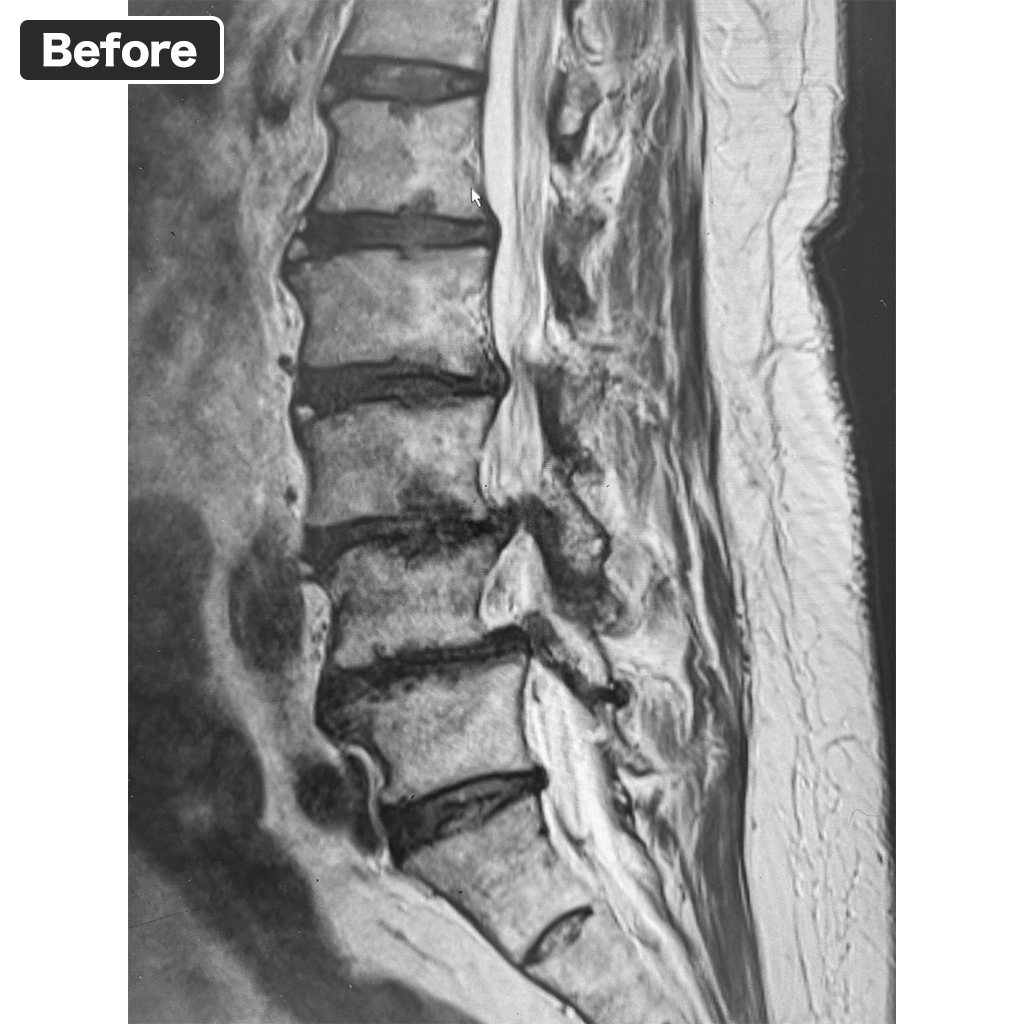

MRI Scan

Pre-treatment MRI scan from 2 years and 6 months ago.